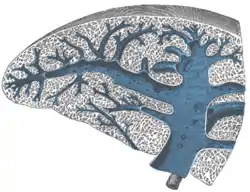

Transverse section of the spleen, showing the trabecular tissue and the splenic vein and its tributaries